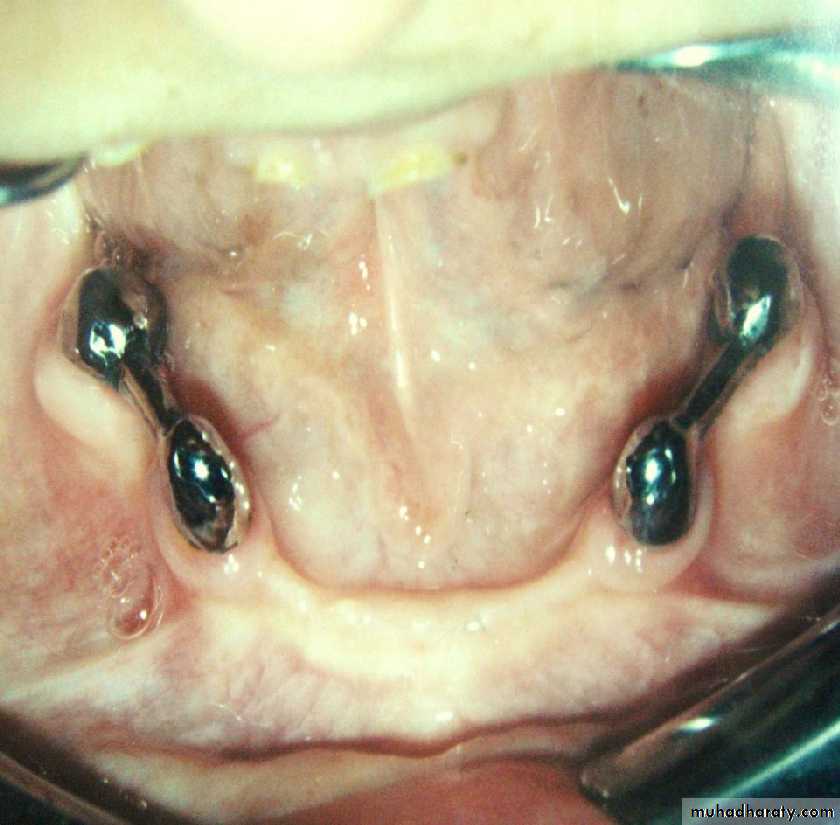

• a) without copings.• Attachment retained overdenture.

• a) stud attachment• b) bar attachment

• c) magnet attachment

• d) telescopic attachment

• Attachment retained overdenture.

• a) stud attachments• Attachment retained overdenture.

• b) bar attachment• Attachment retained overdenture.

• c) magnet attachment• Attachment retained overdenture.

• d) telescopic attachment• 1) Medical history.